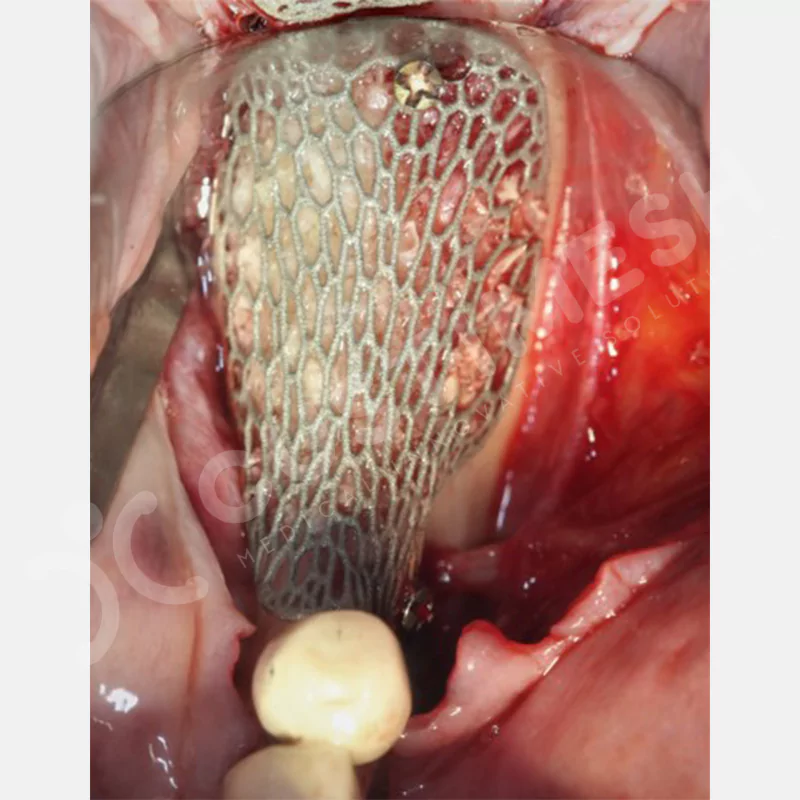

Dental implant uygulanamayan hastalarda kemik rejenerasyonunu sağlamak üzere geliştirilen kişiye özel titanyum mesh, kemik augmentasyon işlemlerinde greft materyalinin korunması ve yeni kemik oluşumunun desteklenmesi amacıyla kullanılan, hastanın kendi anatomisine tam uyumlu titanyum bir bariyer sistemidir.

Medikal sınıf titanyumdan, hastanın bilgisayarlı tomografi verileri kullanılarak CAD yazılımlarıyla tasarlanan ve 3D baskı teknolojisiyle üretilen bu yenilikçi çözüm, özellikle kompleks kemik defektlerinde standart meshlerin sağlayamadığı üstün mekanik stabilite ve mükemmel adaptasyon özellikleri sunar. Anatomik yapıya tam uyum sağlayarak greft materyalinin yerinde kalmasını garanti ederken, optimal vaskülerizasyonu destekleyerek kemik rejenerasyon sürecini hızlandırır.